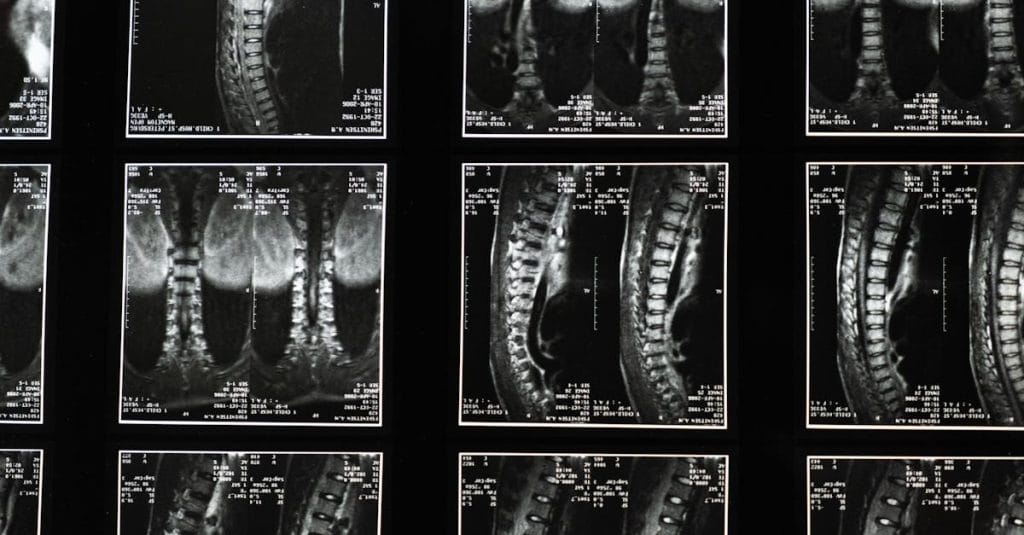

La décompression vertébrale est une approche thérapeutique visant à réduire la pression exercée sur les disques intervertébraux et les nerfs spinal. Cette technique utilise des appareils spécialisés pour créer un environnement propice à la guérison. Les experts en santé choisissent cette méthode car elle réduit de manière significative les douleurs et favorise la circulation sanguine vers les zones affectées.

Comprendre la décompression vertébrale

La décompression vertébrale se réfère à des techniques qui visent à soulager la pression sur les disques intervertébraux et les nerfs. Cette approche est souvent recommandée pour les personnes souffrant de hernies discales, de douleurs lombaires, ou de douleurs cervicales chroniques. En relâchant la pression sur les nerfs et en favorisant une meilleure circulation sanguine autour des structures vertébrales, cette méthode contribue à réduire l’inflammation et à améliorer la mobilité.